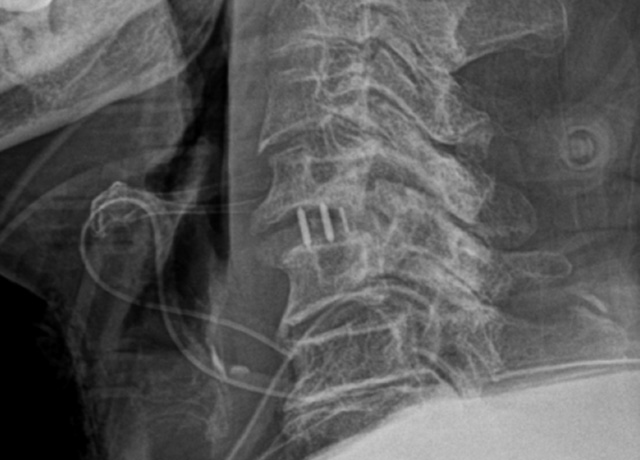

경추 유합술

(ACDF: Anterior Cervical Discectomy and Fusion)